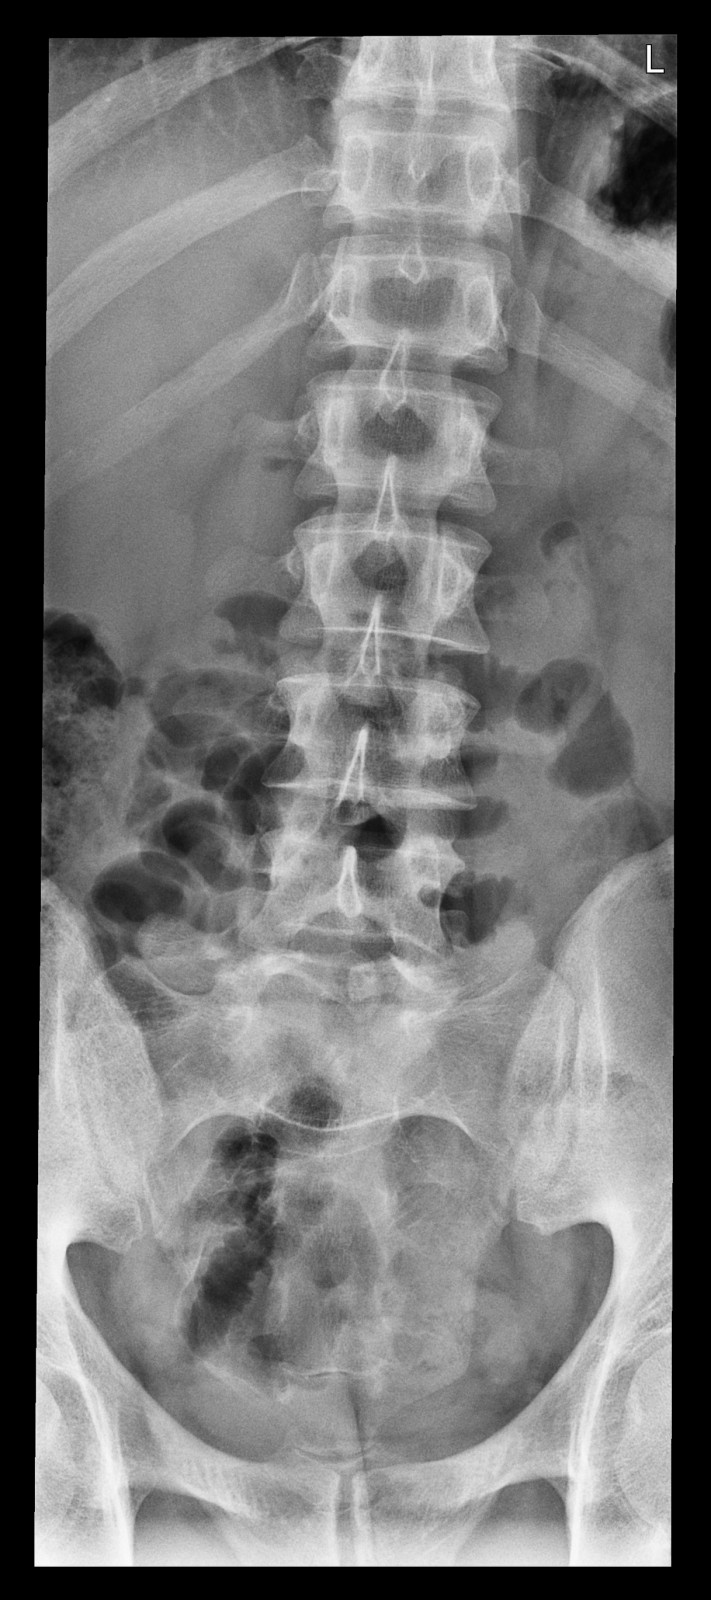

Röntgenfall des Monats Juni 2017 mit Auflösung

34 jähriger Patient mit exazerbierter Lumbago. Beruf: Plattenleger

ap

Bild vergrössern